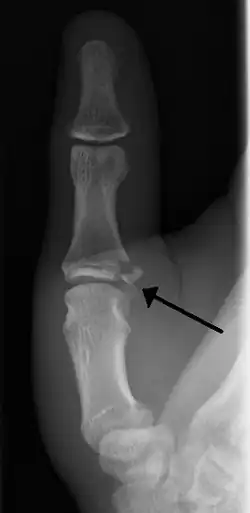

Avulsion fractures of the ulnar base of the proximal phalanx of the thumb ( Gamekeeper's fracture )

• Avulsion of distal UCL causing the pulling off of a bone chip off the proximal phalanx base.[3]

When approaching this type of injury, the physician must first determine whether there is an incomplete rupture (or sprain) of the UCL, or a complete rupture. If the UCL is completely disrupted, the physician must then determine whether there is interposition of the adductor aponeurosis (Stener lesion), or simply a complete rupture of the UCL with anatomic or near-anatomic position. Radiographs are helpful in determining the possible presence of an avulsion fracture of the proximal phalanx insertion site of the ulnar collateral ligament. Stress examination, or one done under fluoroscopic guidance, can help determine the integrity of the ligament.